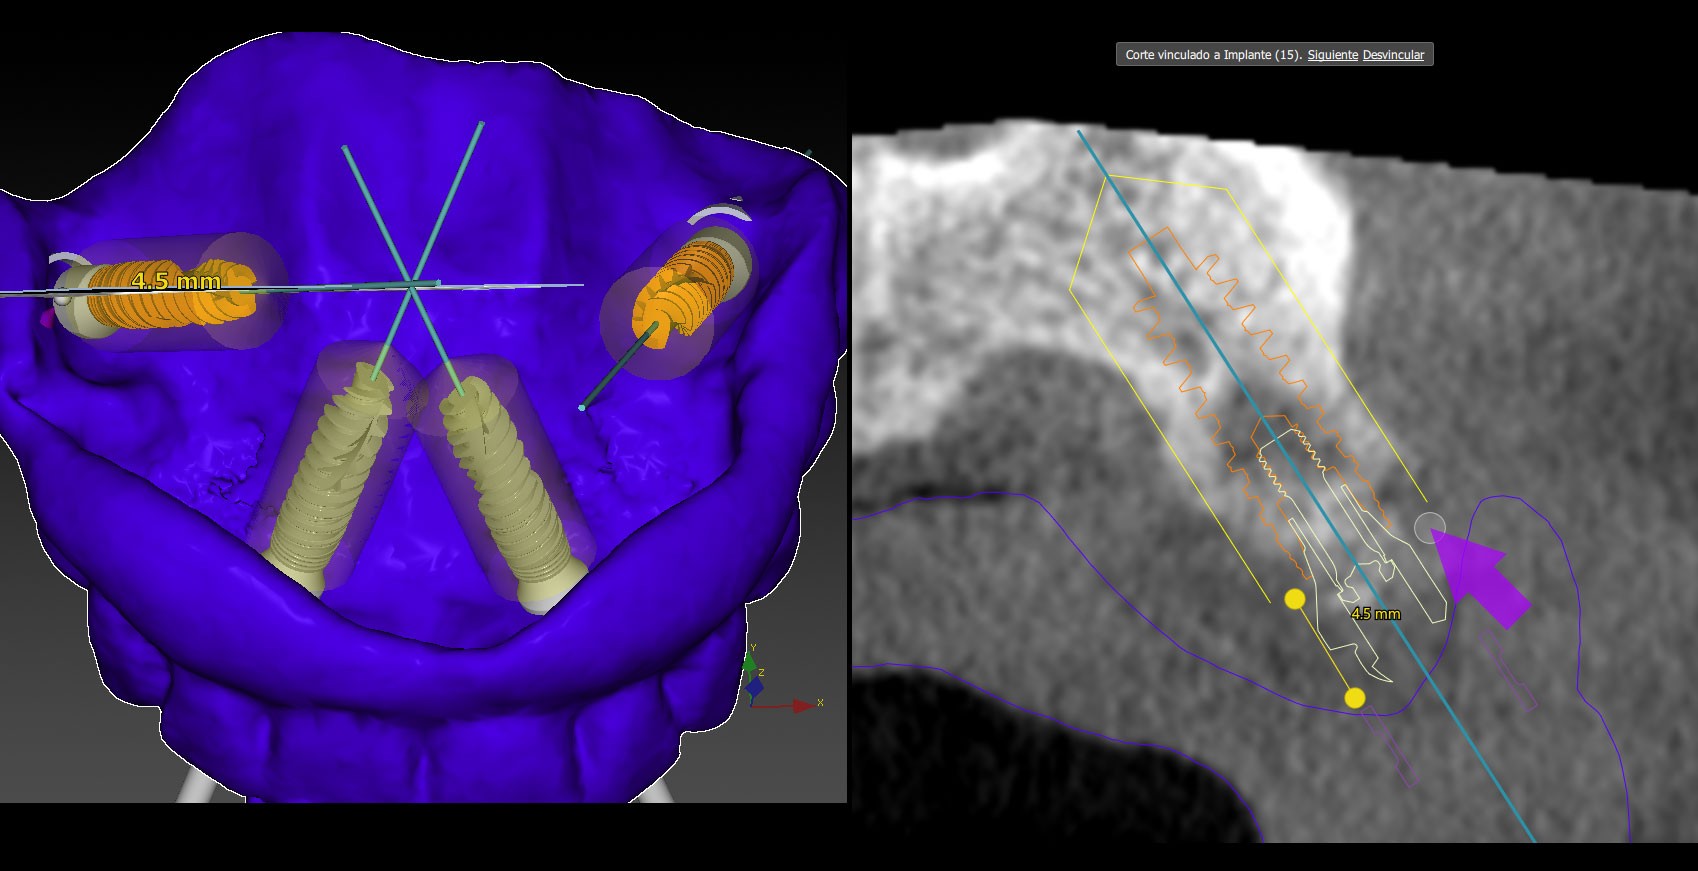

El Doble Factor® es una innovadora técnica para la colocación de Implantes dentales que fusiona la cirugía guiada y navegada en un solo procedimiento más rápido y preciso en pacientes que han perdido toda su dentición.

Se lleva a cabo mediante cirugía mínimamente invasiva, que es guiada mediante navegación monitorizada de la boca del paciente en una pantalla con visión 360º y códigos QR en 3D.

Con unos implantes previamente diseñados, se utiliza la calibración con códigos QR para operar por GPS viendo cómo nos movemos en el hueso del paciente en 360º a tiempo real.

Permite aunar los beneficios de la Cirugía Guiada como primer factor de comprobación y precisión y la exactitud de la Cirugía Navegada.